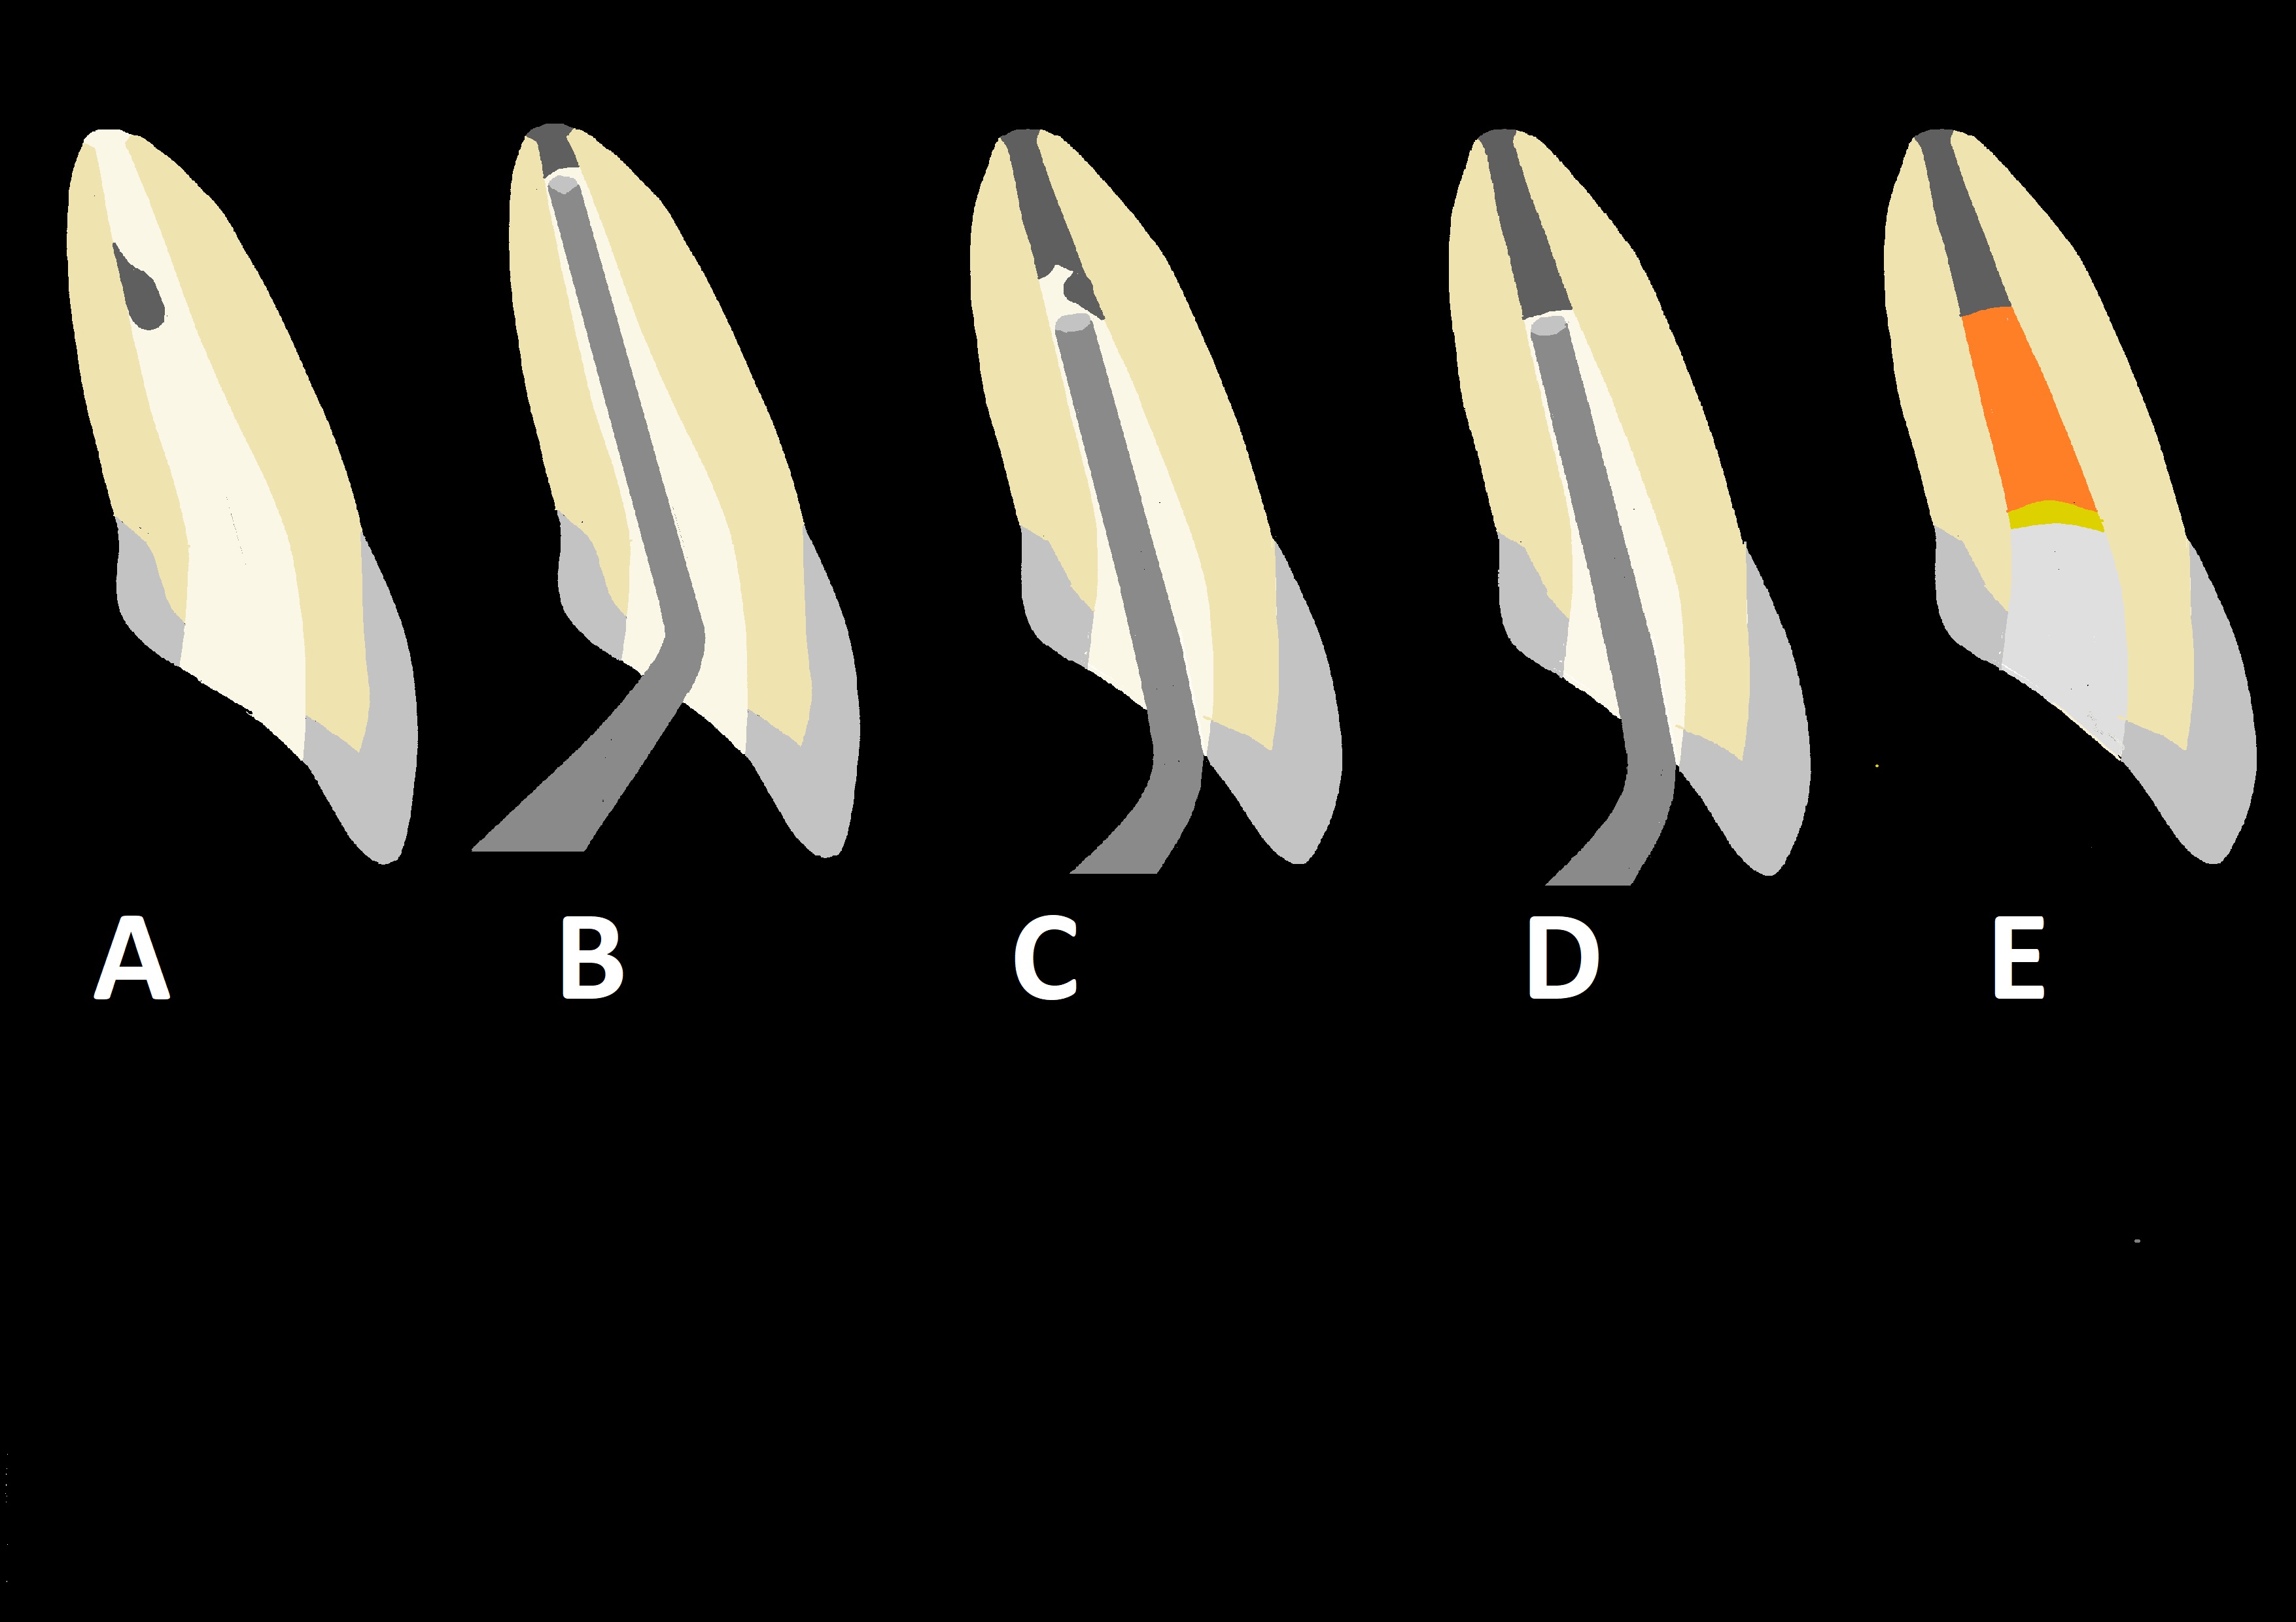

Ryc. 1. Wypełnienie części wierzchołkowej kanału materiałem bioceramicznym (zabieg wykonania „korka”): A. aplikacja pierwszej porcji materiału do kanału; B. kondensacja pierwszej porcji materiału w okolicy otworu wierzchołkowego; C. kondensacja ostatniej porcji materiału; D. kanał wypełniony materiałem bioceramicznym na długości 4-5 mm; E. stan po wypełnieniu części środkowej i koronowej kanału oraz dotworzeniu ubytku w koronie zęba.

Od pewnego czasu do wypełnienia części wierzchołkowej kanału zaleca się, poza preparatami typu MTA, inne bioaktywne cementy zawierające krzemiany wapnia, w tym:

- syntetyczną bioceramikę wymagającą mieszania z odpowiednim roztworem np. BioAggregate (Innovative BioCeramix), Biodentine (Septodont);

- względnie preparaty w postaci jednej pasty niewymagające mieszania np. iRoot BC RRM Putty (Innovative BioCeramix), EndoSequence BC RRM Putty (Brassler), TotalFill BC RRM Putty (FKG), Well-Root PT (Vericom), Bio-C Repair (Angelus).